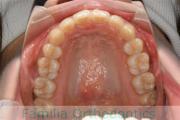

- ≫治療前

上顎

下顎

- ≫治療後

上の前歯が出ているのと下の前歯のでこぼこを治したいということで来院されました。左右のズレがあるので、上顎を左右から、下顎は左下のみ小臼歯を抜歯して、アンカースクリューを併用したマルチブラケット法にて治療を行いました。2年強、25回程度の通院が必要でした。

前歯の移動量が多いケースとなりますので、歯根吸収や歯肉退縮のリスクが高めです。